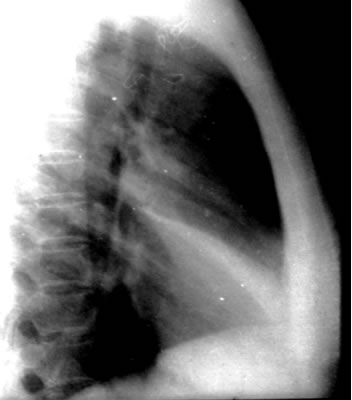

照片名称:右侧胸腔积液